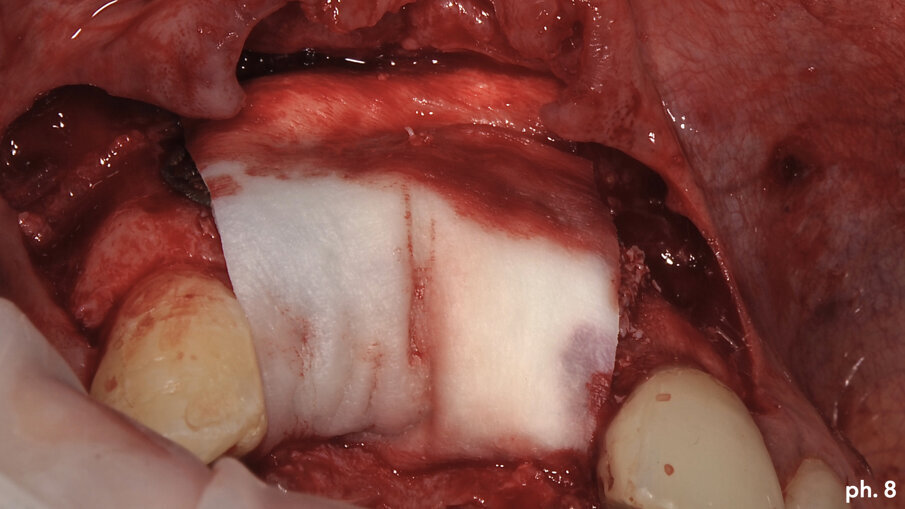

Una volta riempita la griglia con il mix di osso eterologo e autologo, la stessa è stata posizionata a livello del difetto e stabilizzata tramite l’utilizzo di viti di fissazione autofilettanti (Figg. 6, 7). Il grado di stabilità di queste griglie in titanio customizzate CAD/CAM è assolutamente elevatissimo, così come il loro grado di precisione. Stabilizzata in maniera perfetta la griglia, la stessa è stata ricoperta con uno strato di Geistlich Mucograft in modo da permettere la miglior maturazione possibile dei tessuti molli in fase di guarigione (Fig. 8). Al momento della chiusura del lembo è stato necessario effettuare un’incisione per il rilascio del periostio per ottenere una guarigione per prima intenzione, aspetto fondamentale affinché la maturazione di tali presìdi risulti perfetta. Il tempo di guarigione suggerito dalla letteratura prima della rimozione della griglia è di circa otto mesi; personalmente aspetto sempre 12 mesi prima di inserire impianti in una zona di osso rigenerato, e così è stato anche in questa situazione. L’immagine numero 9 rappresenta la guarigione a un anno di distanza e la relativa radiografia di controllo (Fig. 9). L’attesa così prolungata porta a far sì che la fase chirurgica della rimozione delle griglie in titanio sia l’aspetto più complesso di tutto il trattamento. Questo perché le aderenze di tipo fibroso che si creano tra i tessuti molli e la griglia stessa rendono difficile l’asportazione soprattutto a livello palatale e linguale (Fig. 10).